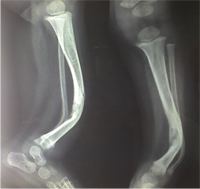

Congenital Pseudarthrosis of the Tibia

Also known as congenital "Anterolateral Bowing of Tibia" or CPT is a rare condition seen in infants and children. The tibia is bowed and the apex of the deformity in anterior and lateral in the sagittal and coronal plane respectively. Incidence is 1: 140,000. This type of bowing is pathognomomic of CPT or Congenital Pseudarthrosis of tibia, leading to a recalcitrant non-union of the tiba and fibula. Almost 50% of cases are associated with Neurofibromatosis type I or fibrous dysplasia. The deformity may be present at birth or occurs as a painless stress fracture when child starts to walk. The typical site of deformity is in the lower third of the leg and both tibia and fibula may be involved. Radiographs reveal typical bowing and the tibia may have sclerotic edges, cortical tapering, cyst formation and sometimes obliteration of meduallary cavity. CPT that Require Treatment

Prognosis doesn't depend on the type of CPT but the extent of involvement of the bone, presence of gap or stiff non-union, and the age of patient at treatment.

Rush Rodding Periosteal Grafting

Newer Fassier - Duval rod in an older child. About CPTCPT is a disorder of the tibia where there is a propensity for recurrent fractures, poor healing of bone and need for multiple operations. Current methods of treatment of CPT have evolved to give much more consistent results than previously possible. Special methods are available to achieve union. |